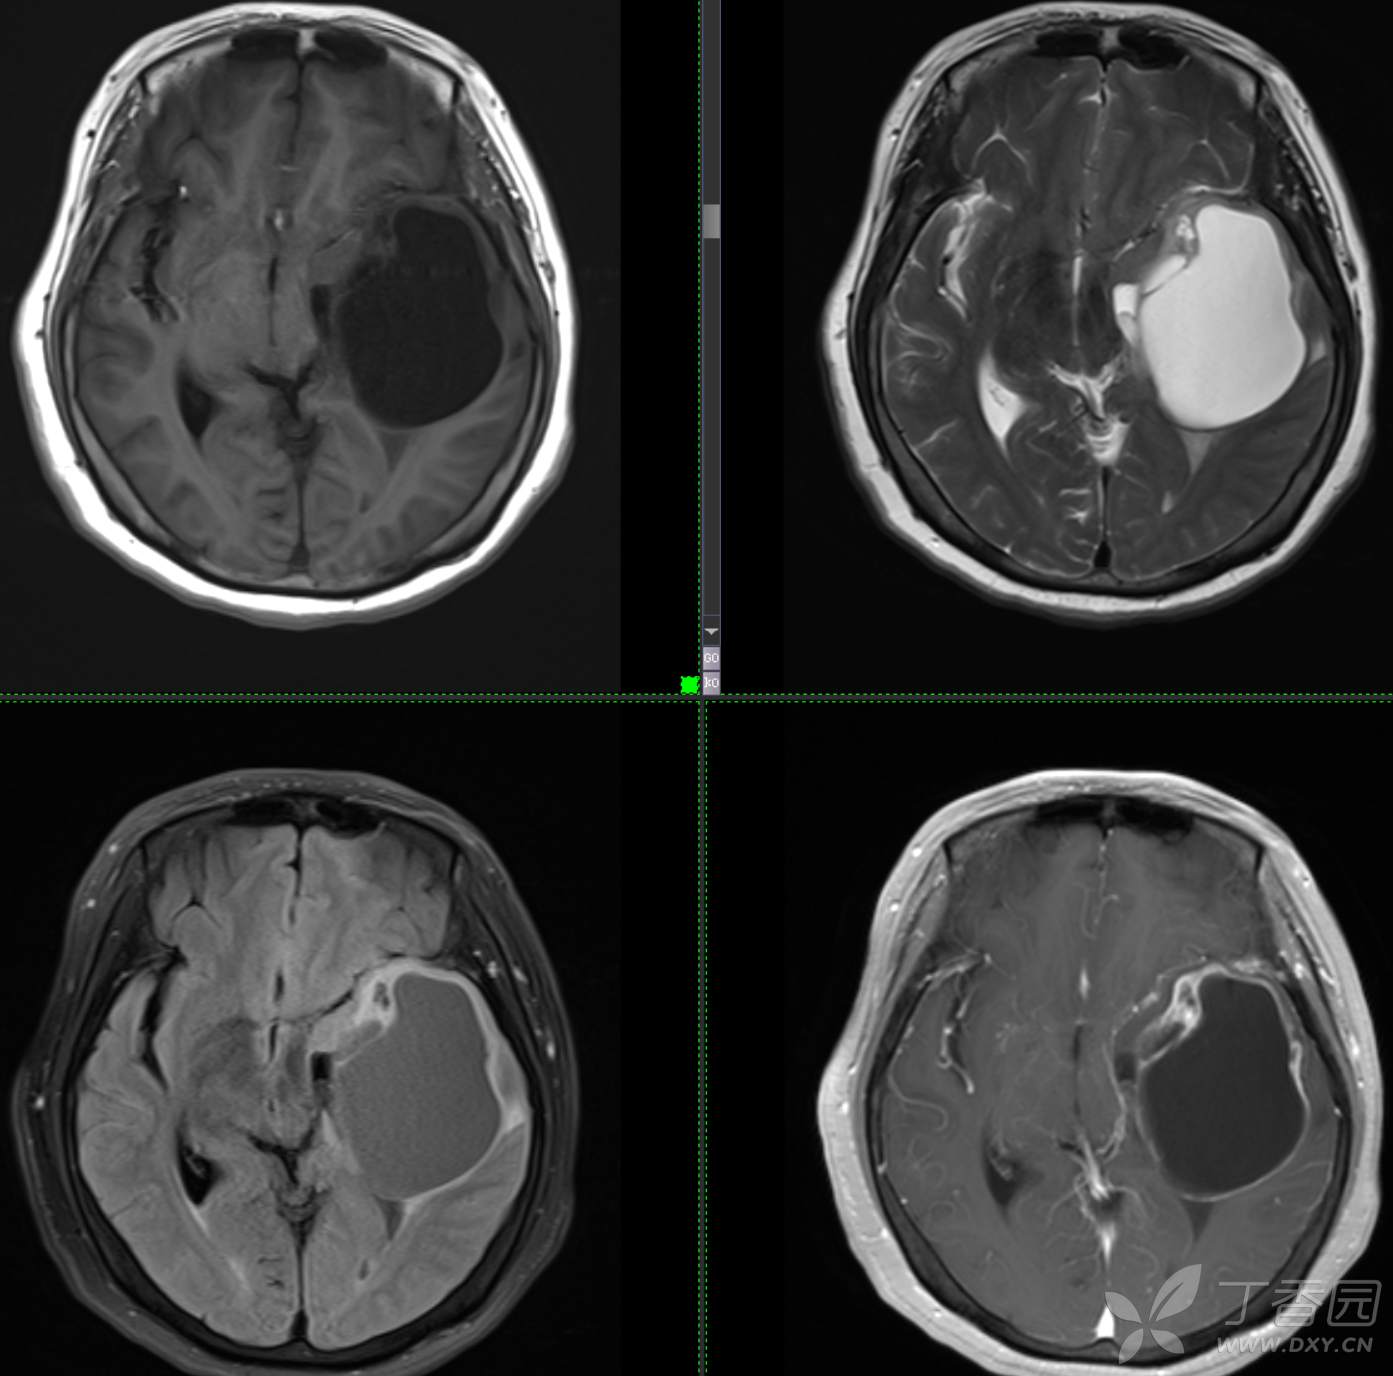

头颈组12:老年女性,原发?继发?

患者年龄:58岁

现病史: 【患者1月余前无明显诱因出现记忆力减退,易忘记事情,表现为忘记说过的话、易忘 事、理解力及计算力均尚可、阅读无受限、无性格脾气改变,无头痛头晕、无恶心呕吐、无视物模糊,无言语不利,无幻觉妄想,当时未重视未就诊。1月内记忆力减退进行性加重,对刚做过的事情即遗忘,计算力下降,日常生活尚能自理。遂至我院门诊就诊,查“颅脑CT平扫:左侧基底节-颞叶区低密度占位,建议进一步增强 MRI检查。

患者既往子宫内膜癌手术史;高血压病史3年